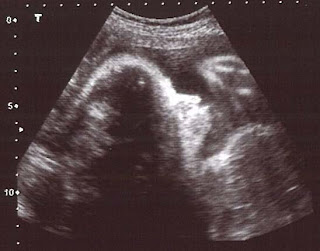

Hoy por fin me han dado buenas noticias en la consulta de ginecología, los niveles de anticuerpos del dichoso Rh parece que están controlados y mi pequeñina ya pesa más de 1,500 Kg. creo que empiezo a respirar más tranquila, seguro que ahora el tiempo va a pasar más deprisa.

Estábamos viendo la carita de mi niña y de repente levantó la manita, ¿estaría saludándonos? :-D